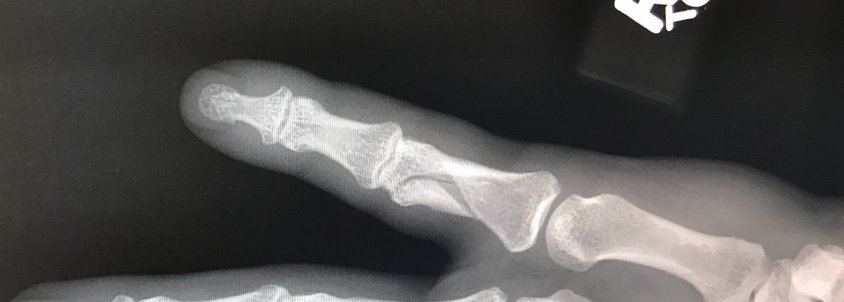

Just a quick update here, I just wanted to let you know that I am not quite out of commission but my hand has been broken. I had a little accident at my baseball game last night and I ended up fracturing my pinky finger. Since it was a full fracture that they elected to do surgery on it which will be taking place later this afternoon.

Here's the picture below of my broken finger, you can see the third bone down in my pinky finger is fractured.

You should recover from this handily Kyle. First if you are right handed it's easier not to put as much stress on it. Second it is longitudinal instead of all the way across the bone and only for a short distance.